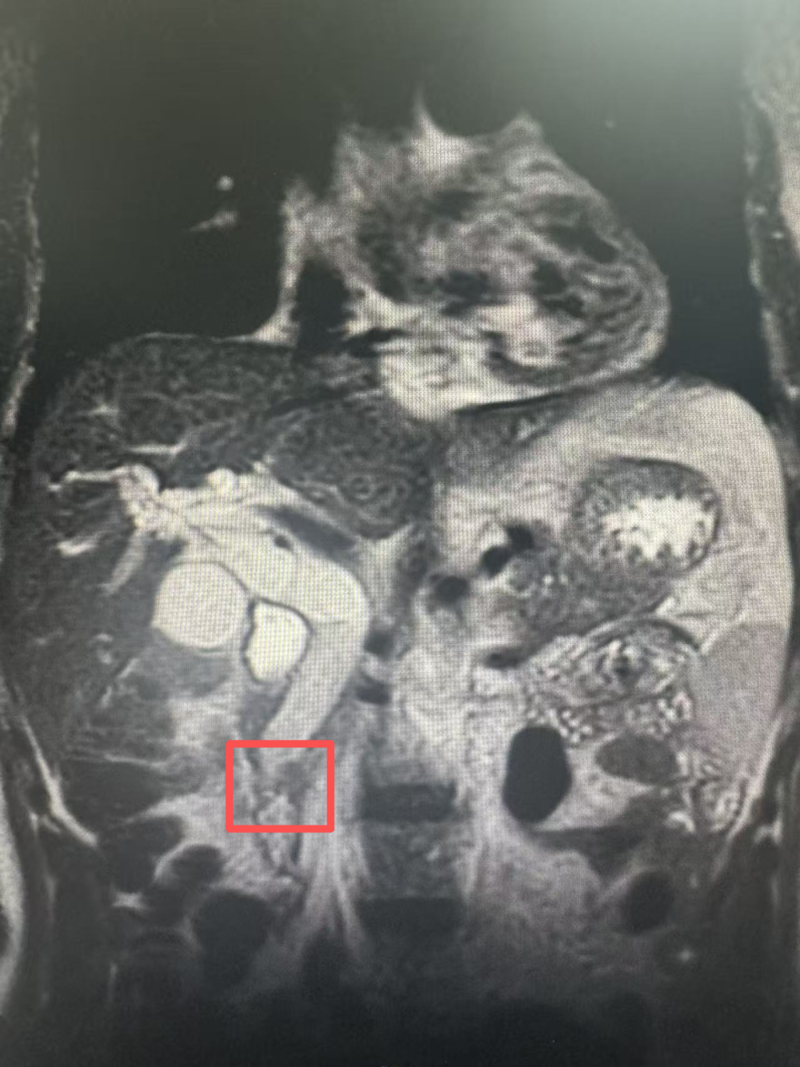

八旬老人突发腿肿,竟是“动脉炸弹”破裂!北大人民青岛医院血管外科顺利拆弹保平安

0天前,85岁的胡爷爷(化名)左腿突然肿胀疼痛,牵连着腹部隐隐发胀。在当地尝试土方子治疗后,症状反而加重。焦急的家人带他来到北京大学人民医院青岛医院血管外科,检查结果并非那么简单。